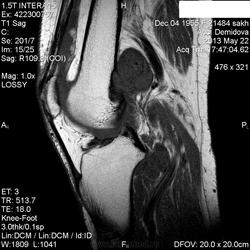

Вчера пациентка на рентгенографию коленного сустава приходила, нашла у нее изменения метадиафиза бедренной кости ( снимки затра выложу-не успеваю) , порекомендовала МРТ.Сегодня она у меня же и проходила исследование. ЗНО однозначно?Либо виллонодулярный синовит? Но разрушение кортикала ? за счет масс-эффекта? не пойму...

По снимкам заподозрила ГКО, АКК и фиброзную дисплазию ( менее вероятно).

Сейчас вообще не пойму-образование , похоже, не из кости растет, а вызывает атрофию ее.Или мне кажется?

Остановилась на пигментном виллонодулярном синовите.

Никогда не видел сам вилонодулярного синовита, но мне кажется Вы правы, по сигнальным харатеристикам на него больше всего похожи изменения. И в большеберцовой кости изменения такие же.

я видел подобное пару раз, только эти "глыбки" были ближе к полости сустава. соглашусь с виллонодулярным синовитом.

С учетом тотальности поражения сустава по DICOM - без вариантов пигментный...

Написала про нерезкую деформацию и ( как мне показалось) кистовидные просветления со склеротическим ободком с признаками нарушения кортикального слоя на задней поверхности в нижней трети метадиафиза бедренной кости.По поводу вариантов были ГКО, АКК .Про пигмнтный синовит как-то даже мысли не было.Зато вспомнила, что пару месяцев назад была подобная коленка с менее выраженным дефектом кости в этом же месте бедра.Я тогда тоже порекомендовала МРТ, но больше пациента не видела.Ему 84 года , поэтому вряд ли родственники оплатят ему исслдование.А данная пациентка пришла на исследование сразу же, на другой день.